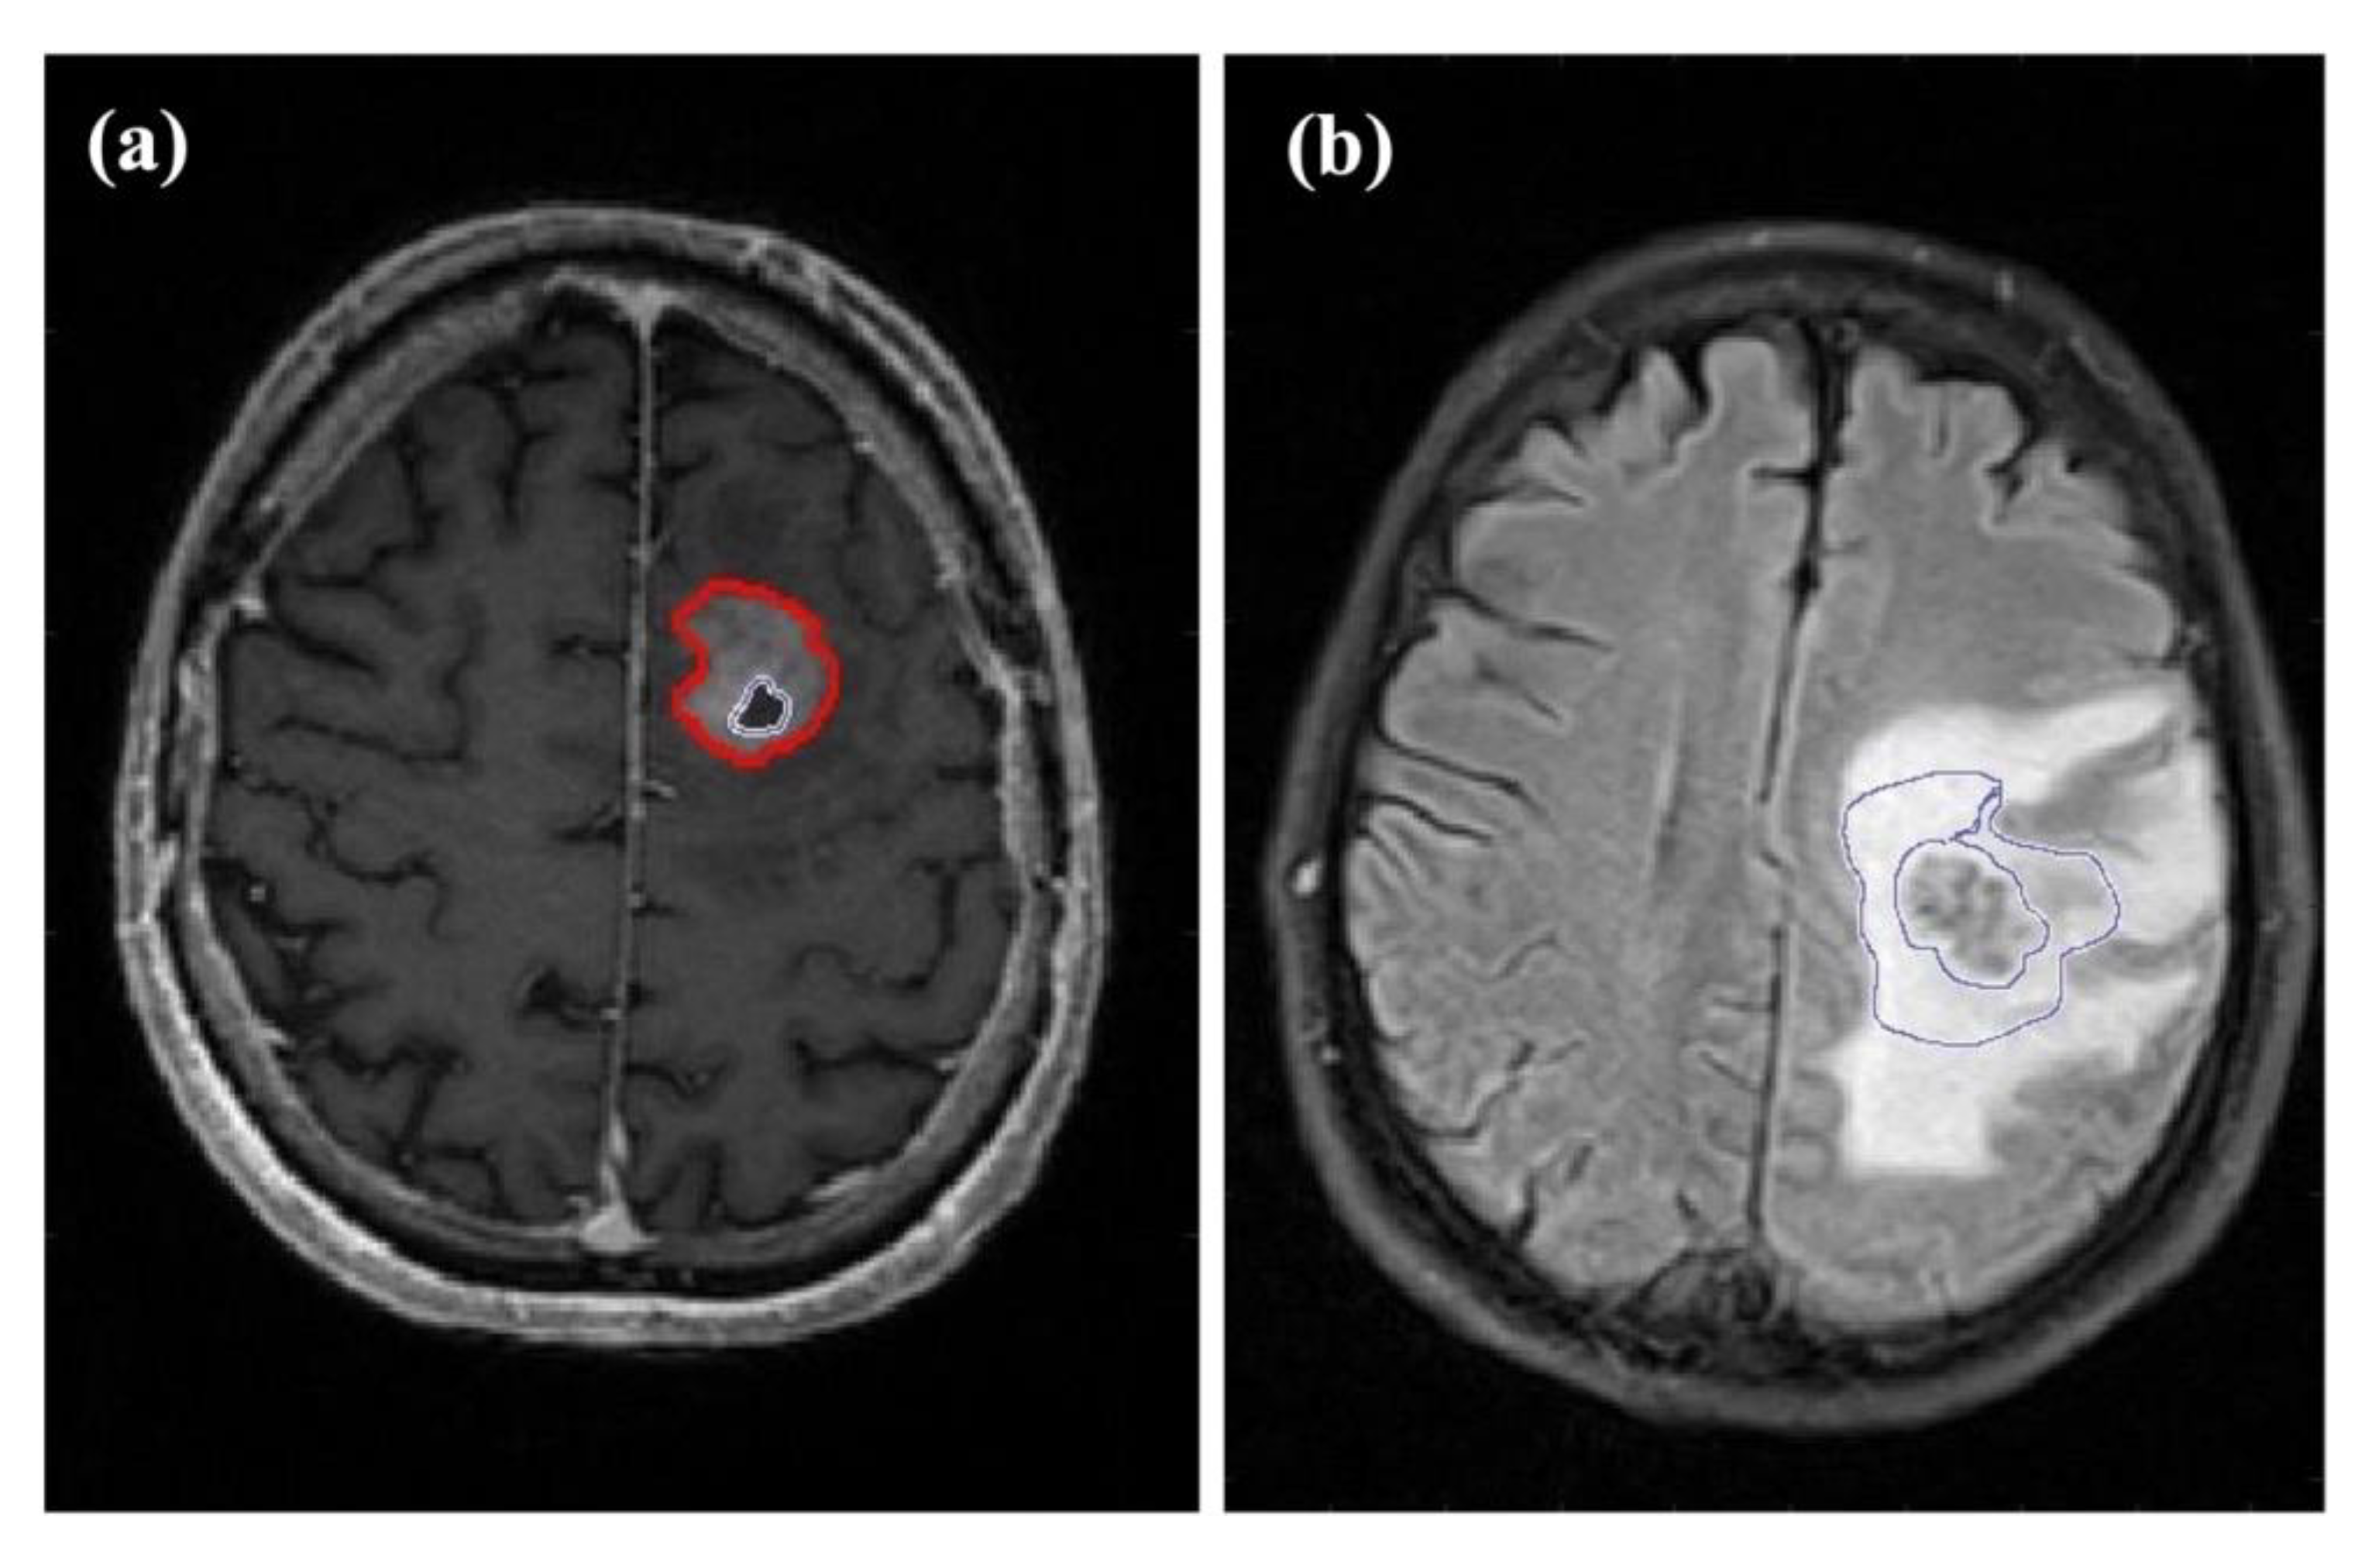

2.1. Patients

2.2. Image Acquisition

2.3. Image Processing

2.4. Calculation of Perfusion and Oxygenation Parameters